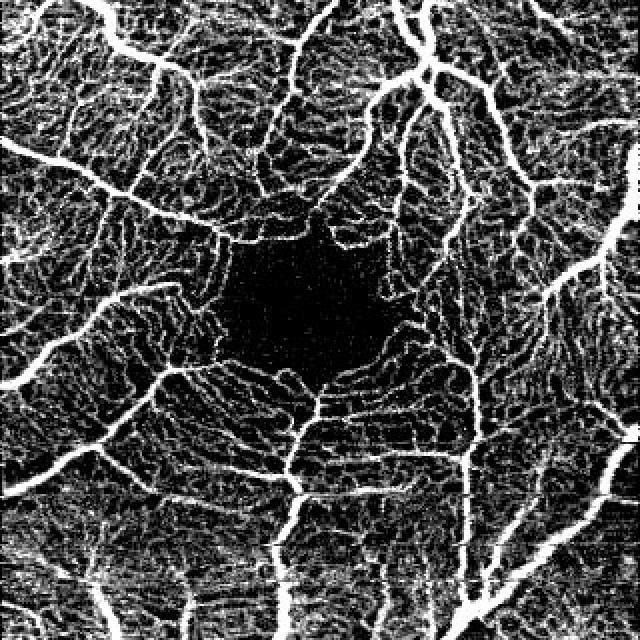

Test our deep learning model for the screening and the classification of diabetic macular ischemia in 3 × 3mm SCP Angiograms.

Grading of diabetic macular ischemia according to ETDRS Report No. 11 : angiograms were classified according the outline of the FAZ and perifoveal capillary loss.

Test the model on these SCP Angiograms

SCP Angiograms of healthy and diabetic eyes from several OCT-A devices with different acquisition quality.

Requirement : a raw 3 × 3mm enface OCTA image segmented to the superficial capillary plexus